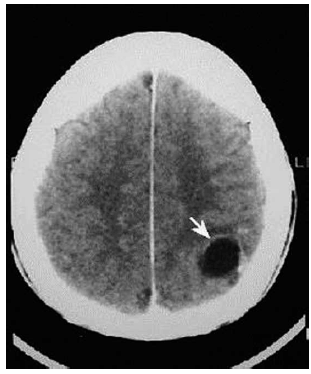

Paciente masculino, 32 anos, previamente hígido, admitido no pronto-socorro com crises convulsivas tônico- clônicas generalizadas. Realizou tomografia de crânio sem contraste em anexo. Assinale a alternativa que apresenta causa mais provável para as crises epilépticas desse paciente.